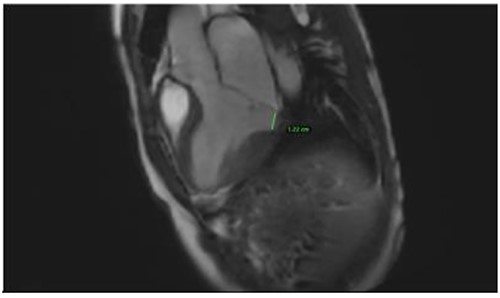

Clinically, both patients complained of worsening palpitations over the last few months with no associated dyspnea or tiredness. A Holter examination recorded 14 444 VES and 212 NSVT, with very similar results in both sisters. The echocardiography revealed a myxomatous Barlow mitral valve with anterior and posterior leaflet prolapse and two regurgitant jets resulting in moderate to severe mitral valve regurgitation as well as mitral annular disjunction in both cases (Figs 1 and 2). A cardiac MRI on a 3 T Lumina Siemens revealed at the mid-left ventricular level, a midwall fibrosis in the midlateral myocardium (Figs 3 and 4) and confirmed a mitral annular disjunction of 12 mm (Figs 5 and 6). Additional findings included a dilated LV with mildly depressed contractility, no visible myocardial scarring, no structural heart disease and a normal sized RV with mildly depressed contractility.

Both sisters underwent a minimally invasive procedure through a right-sided lateral minithoracotomy performed at the level of the third or fourth intercostal spaces. Cardiopulmonary bypass was established through a femoral access and cardioplegic cardiac arrest was achieved through a modified Del Nido solution (20 ml/kg). Mitral valve repair was performed through isolated annuloplasty using in both cases a 38-mm semi-rigid annuloplasty ring. Transesophageal echocardiography after repair revealed excellent surgical results, with no rest regurgitation, no SAM of the mitral valve and most importantly no detectable mitral annular disjunction (Figs 7 and 8). In both cases, being performed several months apart, the patients were extubated in the operating room and transferred to our ICU for further observation.